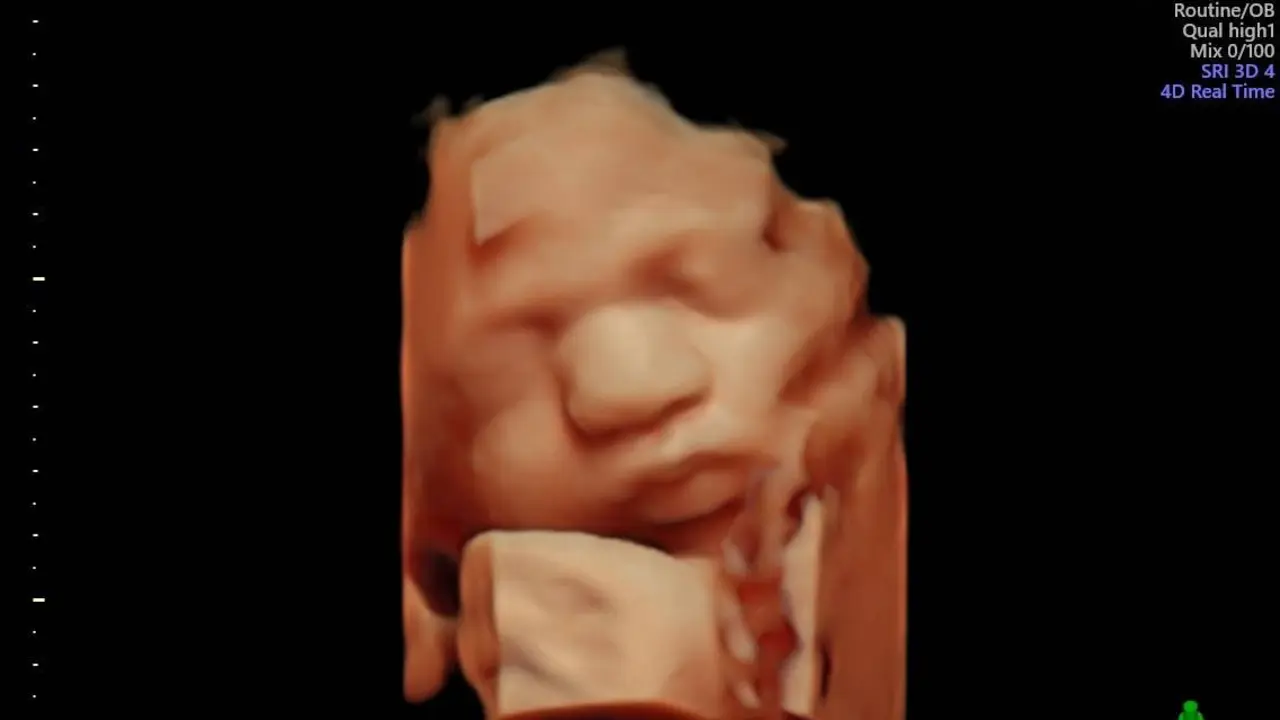

El Hospital Quirónsalud Valle del Henares incorpora un nuevo ecógrafo con tecnología 5D

Este tipo de ecografías permiten a los progenitores obtener imágenes muy realistas de su bebé, además de valorar el estado de bienestar del mismo.